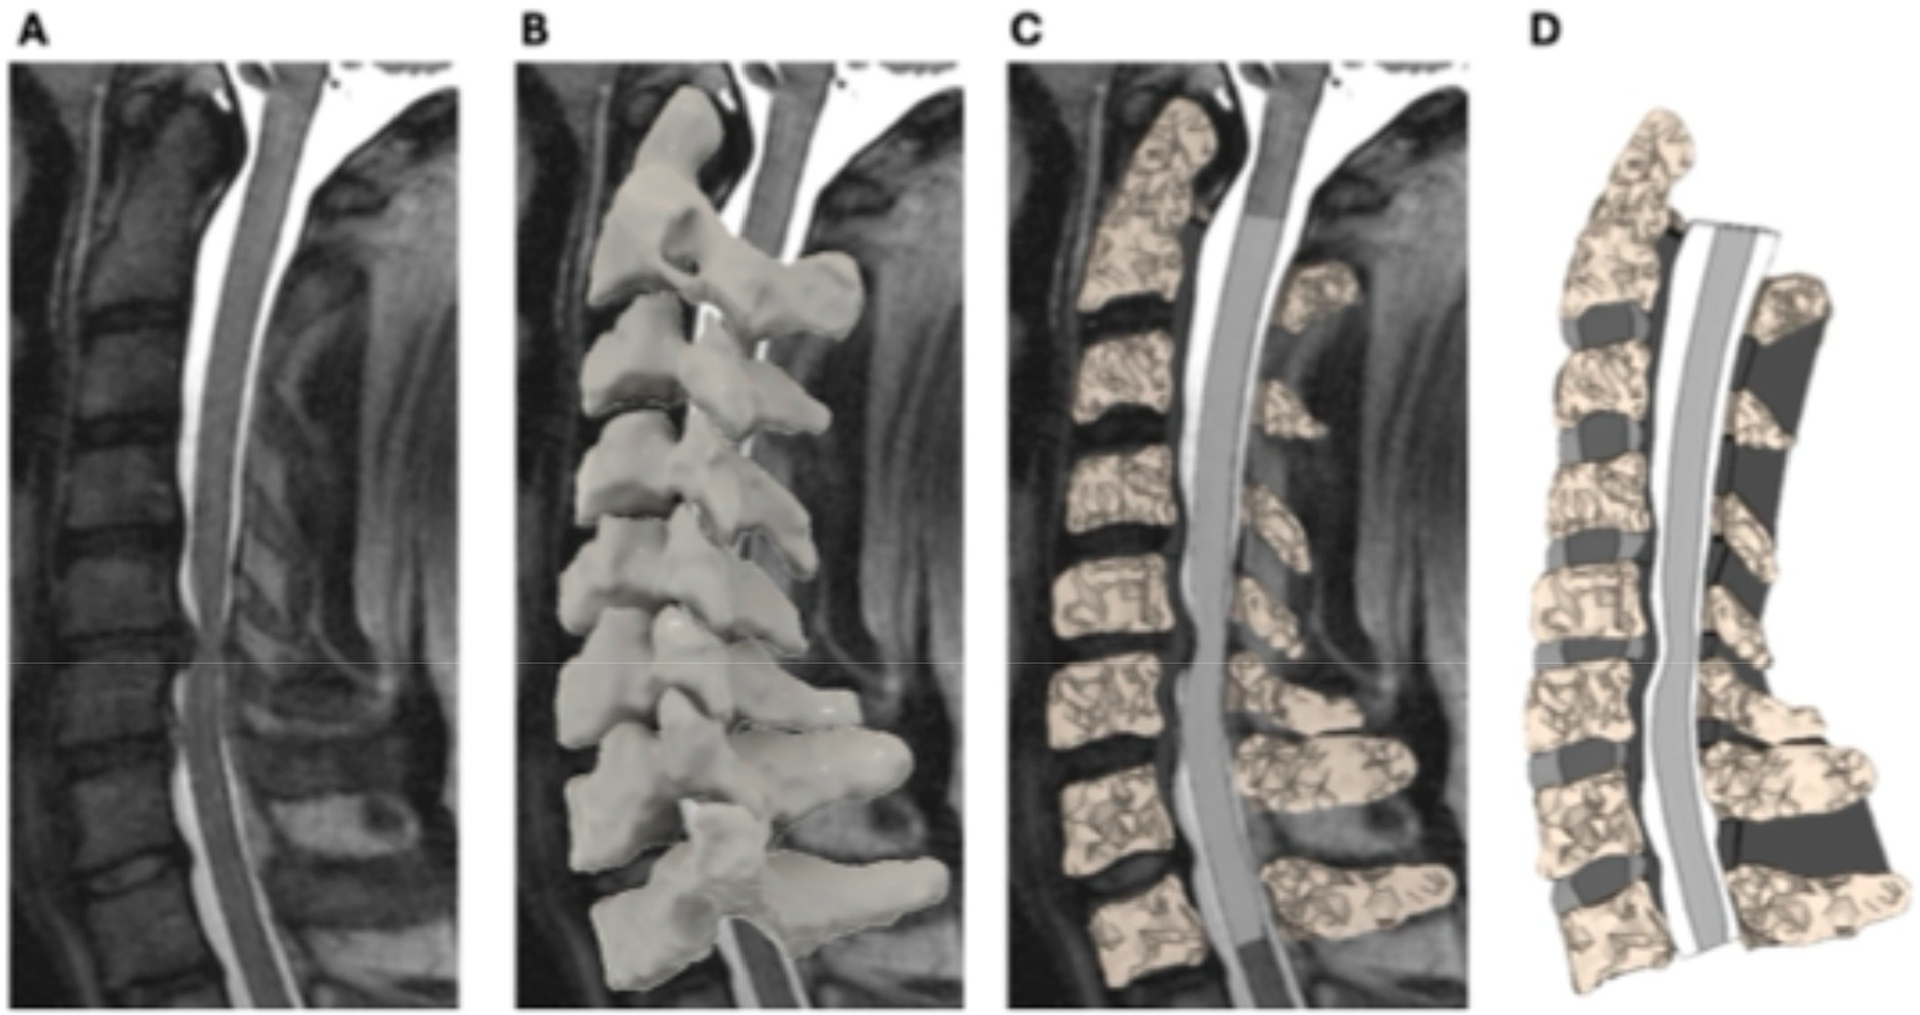

退行性颈椎病(DCM)以进行性神经功能障碍为特征,但颈部运动时髓内应激和劳损的作用尚不清楚。本研究使用患者特定的颈椎和脊髓有限元模型(fem)来检查脊髓生物力学与神经功能障碍之间的关系。DCM患者20例,平均年龄62.7±11.6岁;13名女性)接受了术前基于mri的建模,以量化模拟颈部屈伸时最大脊髓压缩水平下的von Mises应力和最大主应变。术前功能评估包括手感、灵巧性和平衡性。在屈曲过程中,最大压缩水平下的平均髓内应力和应变分别为7.6±3.7 kPa和4.3±2.0%。屈曲时髓内应变增加与右手感觉下降(r = -0.58, p = 0.014)、右手灵巧性受损(r = -0.50, p = 0.048)和灵巧时间延长(r = 0.52, p = 0.039)相关。在髓内应力方面也观察到类似的相关性。重度DCM患者屈曲时的应力明显大于轻度/中度DCM患者(p = 0.03)。这些发现强调了动态脊髓生物力学对神经功能障碍的影响,并支持其在改善DCM诊断和治疗方面的潜在应用。

Degenerative cervical myelopathy (DCM) is characterized by progressive neurological dysfunction, yet the contribution of intramedullary stress and strain during neck motion remains unclear. This study used patient-specific finite element models (FEMs) of the cervical spine and spinal cord to examine the relationship between spinal cord biomechanics and neurological dysfunction. Twenty DCM patients (mean age 62.7 ± 11.6 years; thirteen females) underwent pre-surgical MRI-based modeling to quantify von Mises stress and maximum principal strains at the level of maximum spinal cord compression during simulated neck flexion and extension. Pre-surgical functional assessments included hand sensation, dexterity, and balance. During flexion, the mean intramedullary stress and strain at the level of maximum compression were 7.6 ± 3.7 kPa and 4.3 ± 2.0%, respectively. Increased intramedullary strain during flexion correlated with decreased right-hand sensation (r = -0.58, p = 0.014), impaired right-hand dexterity (r = -0.50, p = 0.048), and prolonged dexterity time (r = 0.52, p = 0.039). Similar correlations were observed with intramedullary stress. Patients with severe DCM exhibited significantly greater stress during flexion than those with mild/moderate disease (p = 0.03). These findings underscore the impact of dynamic spinal cord biomechanics on neurological dysfunction and support their potential utility in improving DCM diagnosis and management.